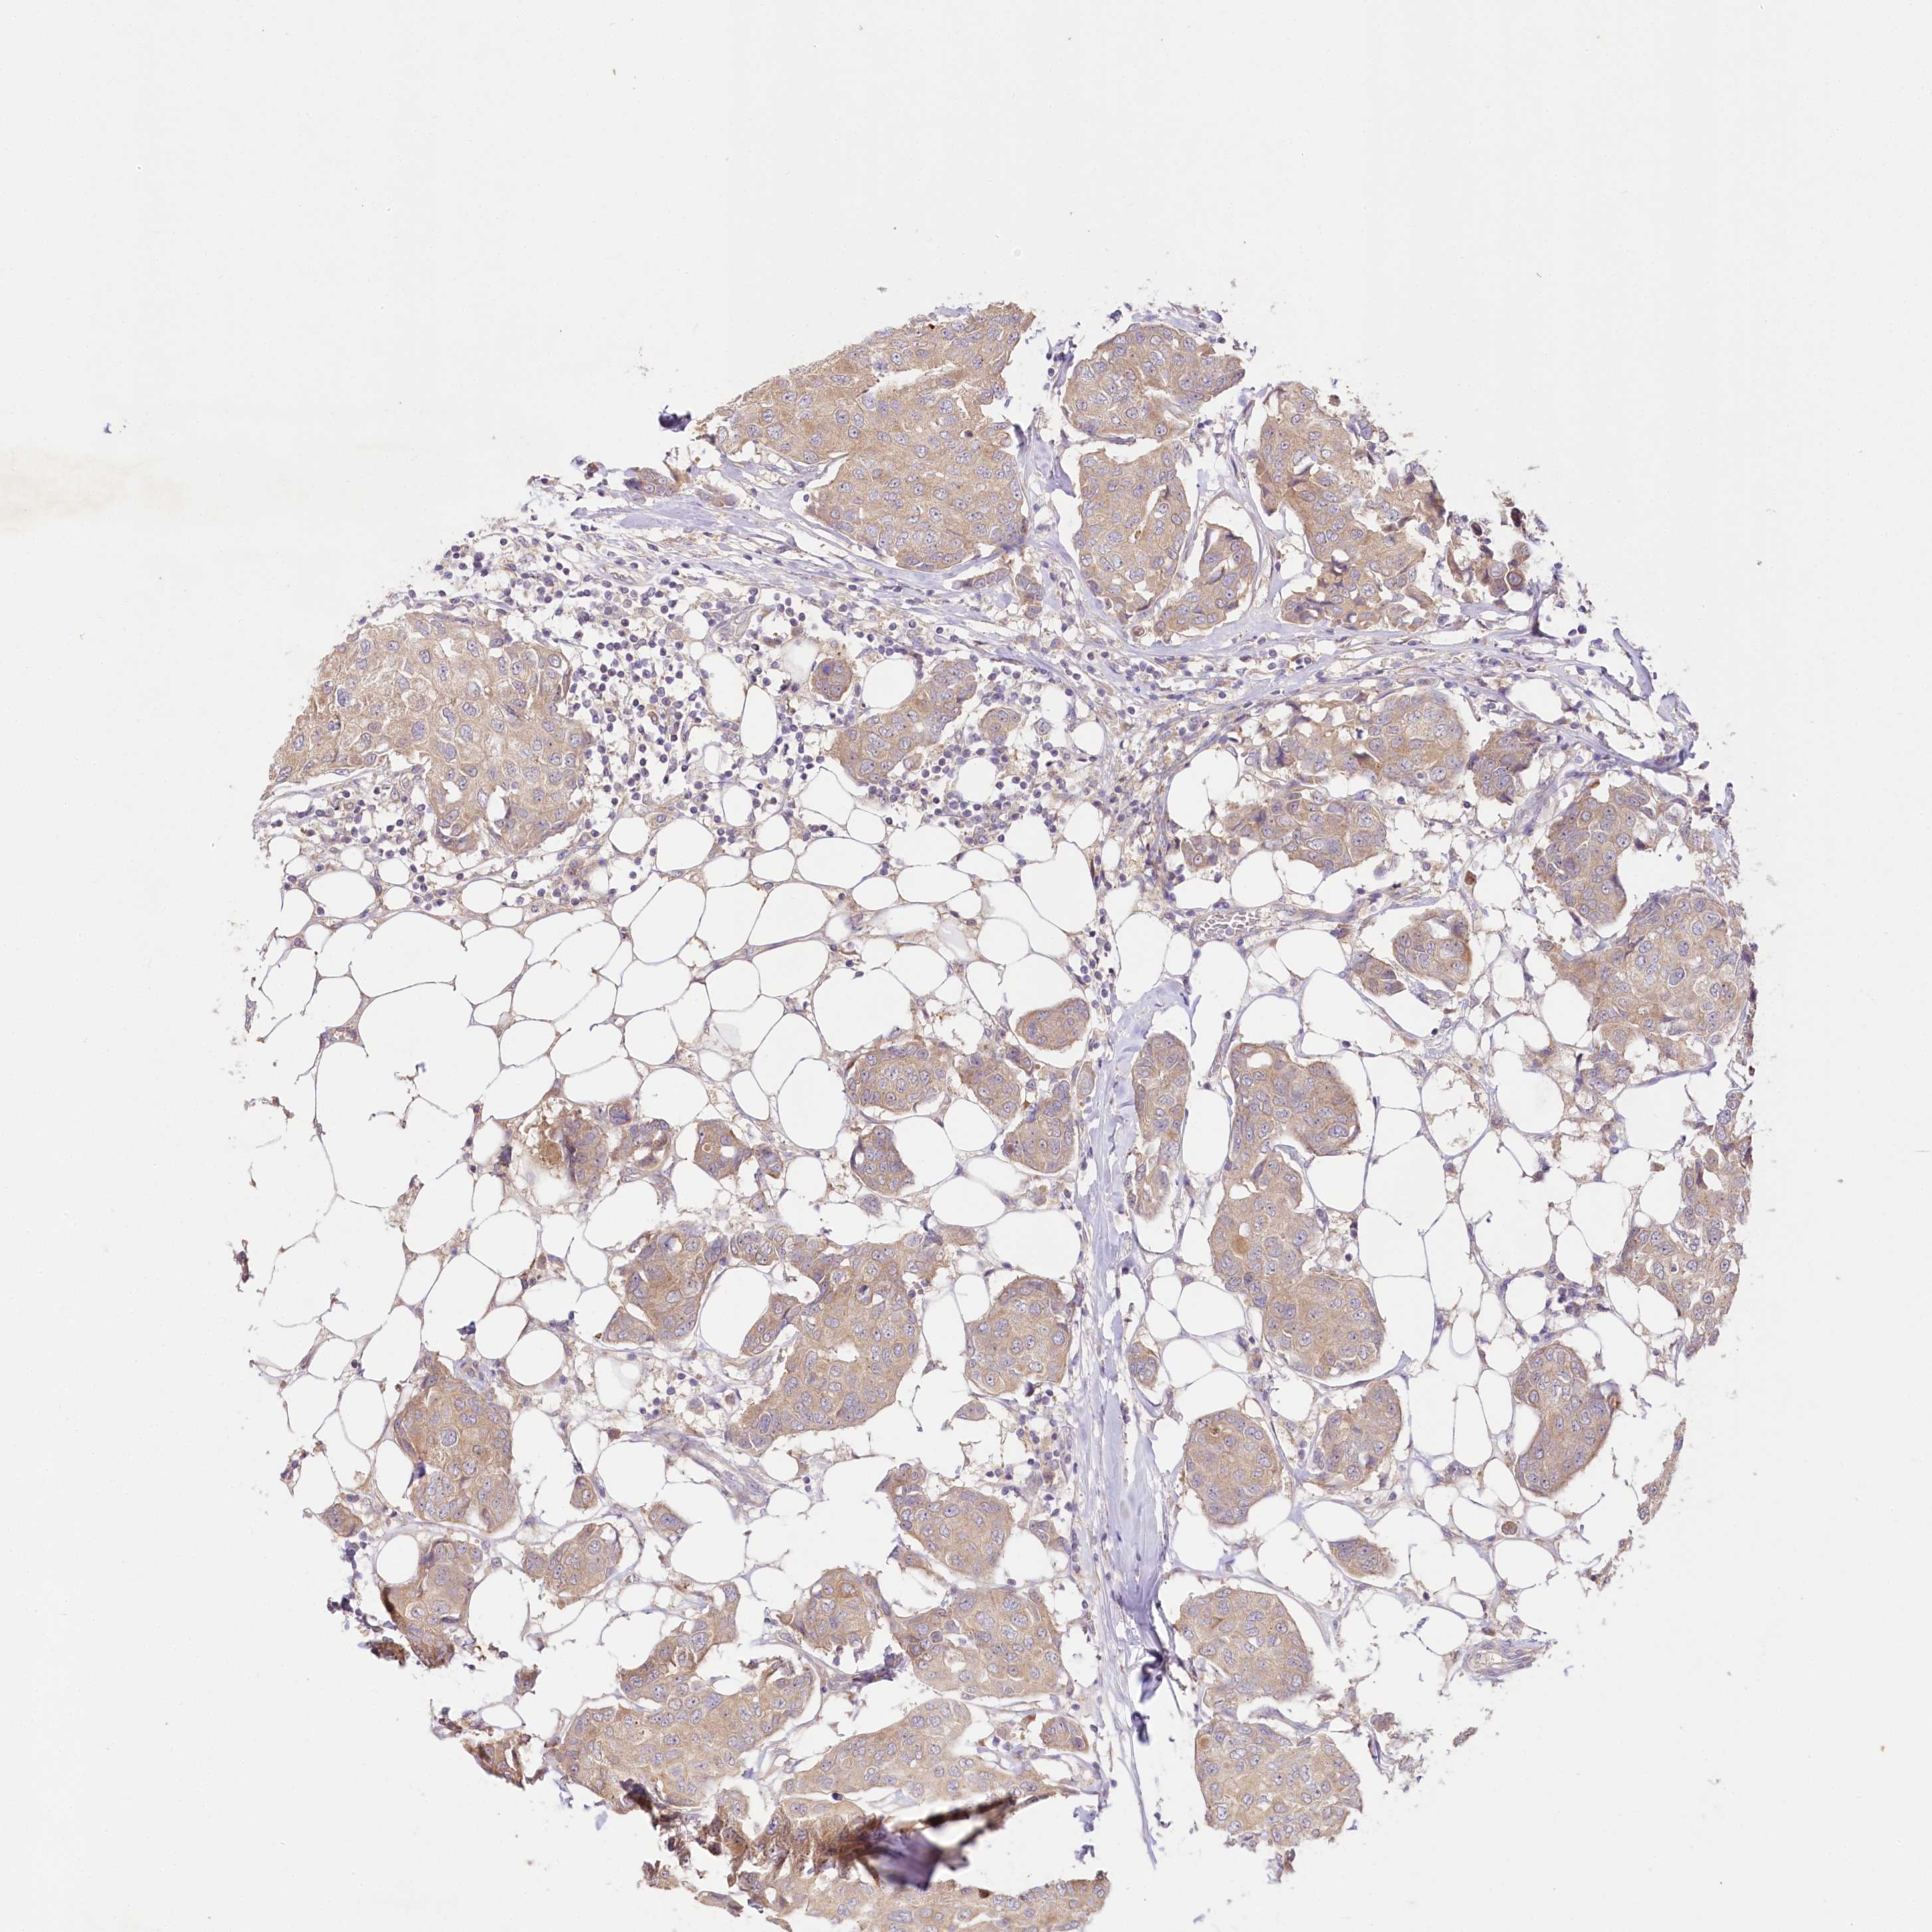

BRCA TCGA BRCA VALIDATION PROTEIN EXPRESSION

ANTIBODIES

AND

VALIDATION